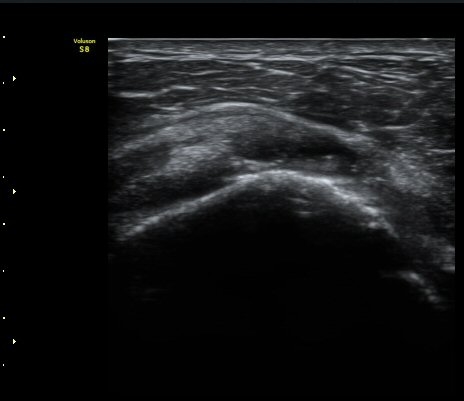

±Ø»ó°Ç Á¾´Ü¸é°Ë»ç»ó ±Ø»ó°Ç ³»Ãø ºÎÂøºÎ¿¡¼­ °Ç¿¬°á¼º ¼Ò½ÇÀÌ °üÂûµÈ´Ù(±×¸² 7, 8).

±Ø»ó°Ç Á¾´Ü¸é°Ë»ç»ó ±Ø»ó°Ç ¼Ò½Ç¿¡ ÀÇÇÑ È¸Àü±Ù°³ °á¼ÕÀÌ °üÂûµÈ´Ù(±×¸² 9, 10).